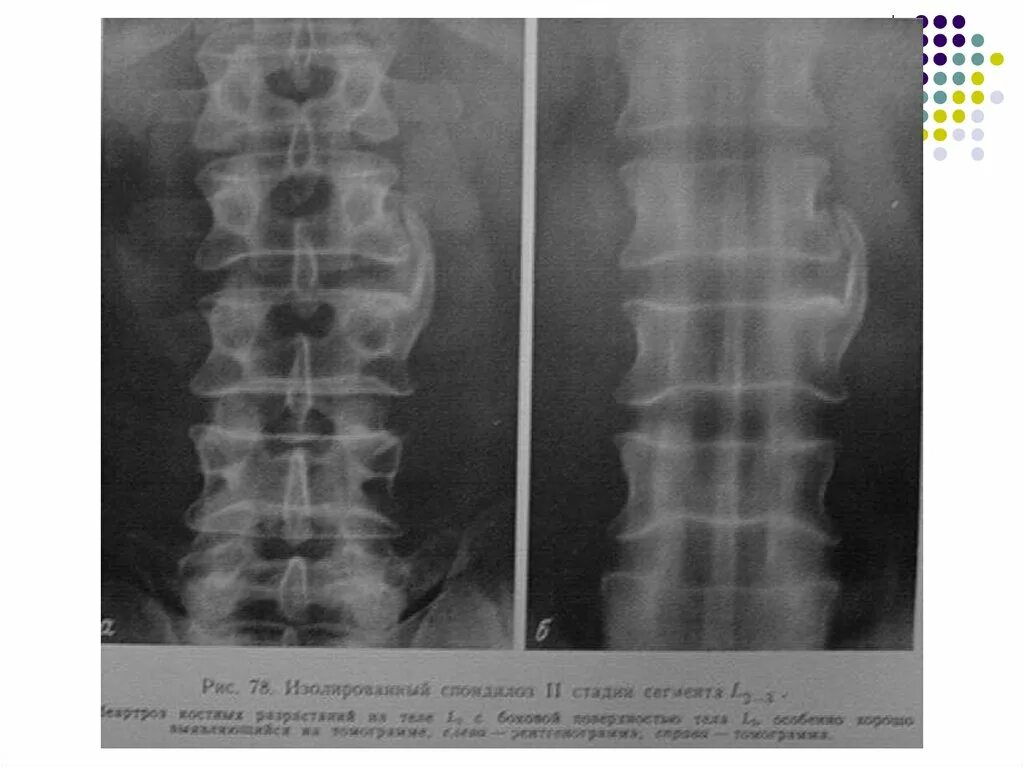

Дистрофия позвоночника поясничного отдела. кт спондилоартроз поясничного отдела позвоночника. мрт позвоночника пояснично-крестцового отдела (l1-s1). дегенеративно-дистрофические изменения позвоночника.Дистрофические изменения пояснично-крестцового отдела позвоночника. дегенеративные изменения пояснично-крестцового отдела. дегенеративные изменения пояснично-крестцового отдела позвоночника. дегенеративно-дистрофические изменения l5-s1.Дегенеративно-дистрофические изменения позвоночника. дегенеративных процессов в межпозвонковых диска. дегенеративные поражения грудного отдела позвоночника. дистрофические изменения пояснично-крестцового отдела позвоночника.Дегенеративные изменения пояснично-крестцового отдела позвоночника. дегенеративно дистрофические поражения позвоночника труфанов. дегенеративно-деструктивные поражения позвоночника. дегенеративно дистрофические изменения l3-l5.Дегенеративные изменения пояснично-крестцового отдела позвоночника. дегенеративно-дистрофические изменения позвоночника на кт. дистрофия изменений пояснично-крестцового отдела позвоночника. дистрофические изменения грудного отдела.Спондилоартроз л3-л5. дегенеративно дистрофические изменения l3-l5. остеохондроз 2 степени поясничного отдела позвоночника. дегенеративно-дистрофические изменения шейного отдела.Дегенеративно-дистрофические заболевания позвоночника. дегенеративно-дистрофические изменения l2 l3. дегенеративные изменения позвоночника. дистрофические изменения позвоночника.Дегенеративно дистрофические изменения пояснично крестцовогоДегенеративные изменения пояснично-крестцового отдела. дегенеративные изменения шейного отдела. дегенеративные изменения пояснично-крестцового отдела позвоночника. дегенеративно-дистрофические изменения позвоночника.Дистрофические изменения пояснично-крестцового отдела позвоночника. дегенеративно-дистрофические изменения l2 l3. дегенеративные изменения пояснично-крестцового отдела. дегенеративно дистрофические в поясничном отделе позвоночника.Дегенеративно дистрофические изменения пояснично крестцовогоДегенеративно дистрофические изменения пояснично крестцовогоДегенеративно дистрофические изменения пояснично крестцовогоДегенеративно дистрофические изменения пояснично крестцовогоДегенеративные изменения грудного отдела позвоночника. дегенеративные изменения грудного позвоночника. дегенеративные изменения дисков грудного отдела позвоночника. дегенеративно деструктивные изменения позвоночника.Дегенеративно деструктивные заболевания позвоночника. ддзп пояснично- крестцового отдела. дистрофически дегенеративные изменения позвоночника. дегенерация поясничного отдела позвоночника.Дегенеративно дистрофические изменения пояснично крестцовогоДегенеративно дистрофические изменения пояснично крестцовогоДегенеративно-дистрофические изменения позвоночника. дистрофические изменения грудного отдела позвоночника. дистрофические изменения th1-th12. дегенеративные дистрофические изменения пояснично-крестцовый отдел.Дегенеративные-дистрофических изменений l1-s1. дегенеративные изменения грудного отдела позвоночника. мр-картина дистрофических изменений грудного отдела позвоночника. дегенеративные изменения поясничного отдела l5-s1.Дегенеративно-дистрофические заболевания позвоночника (ддзп). межпозвонковый остеохондроз (поражение до 3 межпозвонковых дисков). дегенеративно-дистрофические поражение позвоночника диагноз. дегенеративно-дистрофические изменения l2 l3.Дегенеративные изменения l5 s1. дегенеративно-дистрофические изменения l5-s1. грыжа пояснично-крестцового отдела позвоночника l5-s1. дегенеративные изменения поясничного отдела l5-s1.Дегенеративно дистрофические изменения пояснично крестцовогоДегенеративно-дистрофические изменения позвоночника на кт. дегенеративные изменения пояснично-крестцового отдела. дегенеративные изменения позвоночника на кт. дегенеративные изменения поясничного отдела позвоночника.Дегенеративно дистрофические изменения пояснично крестцовогоДегенеративно дистрофические изменения пояснично крестцовогоДегенеративно дистрофические изменения пояснично крестцовогоКраевые костные разрастания тел позвонков шейного отдела. спондилез остеофиты. спондилоартроз l3-s1. остеофиты позвоночника поясничного отдела.Дегенеративно-дистрофические изменения позвоночника. этапы развития остеохондроза позвоночника. дегенеративные изменения грудного отдела позвоночника. дегенеративные заболевания диска межпозвоночного диска.Дегенеративно дистрофические изменения пояснично крестцовогоДегенеративно-дистрофические изменения позвоночника мрт. дегенеративные изменения. дегенеративные изменения поясничного отдела. дистрофические изменения шейного позвоночника.Дегенеративно-дистрофические изменения рентген. деструктивные изменения в позвоночнике что это. рентгенодиагностика позвоночника. дистрофические изменения позвоночника.Дегенеративно-дистрофические изменения позвоночника мрт. жировая дегенерация мрт. жировая дегенерация позвонков поясничного отдела позвоночника.Дегенеративные изменения позвоночника мрт. дистрофические изменения грудного отдела позвоночника. дегенеративно-дистрофические изменения l2 l3. дегенеративные изменения поясничного отдела позвоночника.Дегенеративно-дистрофические изменения l4-s1. секвестрированная грыжа l4-5. парамедианная грыжа диска l4-5 что это. парамедианная грыжа l4-l5.Дегенеративные дистрофические дистрофические изменения. дегенеративно дистрофические изменения отдела позвоночника. дегенеративно-дистрофические изменения l2 l3. дегенеративно-дистрофические изменения шейного отдела.Краевые остеофиты позвонков поясничного отдела. дегенеративно-дистрофические заболевания позвоночника (ддзп). остеохондроз s1 s2 позвонка. краевые остеофиты тел позвонков что это такое.Дегенеративно-дистрофические изменения позвоночника на кт. остеохондроз s1 s2 позвонка. дегенеративно дистрофические изменения грудного отд позвоночника. дистрофические изменения позвоночника грудного отдела 1-2 степени.Дистрофические изменения позвоночника. дегенеративные изменения пояснично-крестцового. дистрофические изменения пояснично-крестцового отдела. дегенеративные процессы в позвоночнике.Дегенеративно-дистрофические поражения позвоночника. дистрофические изменения позвоночника. дегенеративные изменения позвонков. дегенеративные изменения грудного отдела позвоночника.Дегенеративные поражения грудного отдела позвоночника. дегенеративно-дистрофическое поражение шейного отдела. дегенеративно-дистрофические изменения позвоночника. дистрофические изменения шейного.Дегенеративно дистрофические изменения пояснично крестцовогоСпондилоартроз l2-s1 что это такое. спондилоартроз спондилез остеохондроз. спондилоартроз пояснично-крестцового отдела позвоночника. спондилоартроз с2 с3.Дистрофические изменения межпозвонковых дисков шейного отдела. дегенеративно-дистрофические изменения l2 l3. ддзп поясничный остеохондроз. остеохондроза дисков пояснично-крестцового отдела.Дегенеративно-дистрофические изменения позвоночника. дегенеративные изменения позвонка. дистрофические изменения позвонков. дегенеративные изменения тел позвонков.Дегенеративно-дистрофическое поражение шейного отдела. дорсопатия дегенеративно-дистрофических изменений позвоночника. дегенеративно-дистрофические изменения l2 l3. дегенеративные изменения шейного отдела позвоночника.Межпозвоночный диск. дегенеративные изменения межпозвонковых дисков. межпозвоночные хрящевые диски. дегидратация межпозвонковых дисков.Рентгенологические признаки дегенеративно-дистрофических изменений. рентген поясничного отдела позвоночника сбоку. дистрофические изменения позвоночника. дегенеративно-дистрофические изменения позвоночника.Поясничный остеохондроз симптомы. дистрофические изменения. воспаление межпозвонкового диска. дегенеративно-дистрофические изменения легких.Дегенеративные изменения позвоночника. дегенеративные изменения поясничного отдела позвоночника. дегенеративное извинения позвоночника. дегенеративное повреждения позвоночника.Дегенеративно дистрофические изменения пояснично крестцовогоГрыжи позвоночника топографическая анатомия. сегменты поясничного отдела позвоночника. снижение высоты межпозвоночного диска. сегменты межпозвонковых дисков.Дегенеративно дистрофические изменения пояснично крестцовогоДегенеративно дистрофические изменения пояснично крестцовогоДегенеративно дистрофические изменения пояснично крестцовогоДегенеративно-дистрофические изменения позвоночника. остеохондроз спондилоартроз. спондилоартроз пояснично-крестцового отдела позвоночника корсет.Этапы развития остеохондроза позвоночника. хондроз 2 степени поясничного отдела. степени и периоды остеохондроза шейного отдела. хондроз шейного отдела начальная стадия.Дегенеративно дистрофические изменения пояснично крестцовогоДегенеративные изменения шейного отдела. с остеохондрозом берут в армию. дорсалгия позвоночника. берут ли в армию с остеохондрозом поясничного отдела.Дорсопатия пояснично-крестцового отдела позвоночника. дорсопатия дегенеративно-дистрофических изменений позвоночника. дегенеративно-дистрофические изменения l2 l3. радикулит у собак лечение.Дегенеративно дистрофические изменения пояснично крестцовогоСпондилоартроз пояснично-крестцового отдела. артроз дугоотросчатых суставов поясничного отдела. спондилоартроз на уровне th12-s1. спондилоартроз l2-s1 что это такое.Дегенеративно дистрофические изменения пояснично крестцовогоДегенеративно дистрофические изменения пояснично крестцовогоДегенеративно-дистрофические изменения позвоночника рентген. дегенеративный стопделит. дегенеративный спондилит. умеренные дистрофические изменения грудного отдела позвоночника.Заболевания грудного отдела позвоночника названия. изменения позвоночника. дегенеративные заболевания позвоночника. дистрофические поражения позвоночника.Дегенеративно дистрофические изменения пояснично крестцовогоДегенеративно дистрофические изменения пояснично крестцовогоДегенеративно дистрофические изменения пояснично крестцовогоДегенеративно-деструктивные изменения межпозвоночного диска. дегенеративно дистрофические изменения отдела позвоночника. дегенератмвноедистрафические изменения позвоночника. дистрофические изменения грудного отдела.Протрузия позвонков поясничного отдела. остеохондроз протрузии межпозвонковых дисков. протрузия межпозвонковых дисков крестцового отдела. протрузия диска th1/th2.Дегенеративно деструктивные заболевания позвоночника. дегенеративно дистрофические изменения грудного отд позвоночника. генеративное изменение позвоночника. дистрофические изменения шейного позвоночника.Грыжа s1-s2. мрт l4-s1 расшифровка. грыжа между 4 и 5 позвонком поясничного. 4 поясничный позвонок.Дегенеративно дистрофические изменения пояснично крестцовогоДегенеративно дистрофические изменения пояснично крестцовогоЛфк при дегенеративно дистрофических изменениях позвоночника. гимнастика для поясницы при дегенеративных изменениях позвоночника. лфк при дегенеративных изменениях в структурах позвоночника. лфк при дегенеративно дистрофических изменениях шейного отдела.Дегенеративно дистрофические изменения пояснично крестцовогоДегенеративные заболевания диска межпозвоночного диска. дегенеративно-дистрофические изменения позвоночника. дистрофические изменения грудного отдела позвоночника. стадии дегенеративно-дистрофические заболевания позвоночника.Дегенеративно дистрофические изменения пояснично крестцовогоДдзп шейно грудного отдела позвоночника. дегенеративные заболевания диска межпозвоночного диска. дегенеративно-дистрофические заболевания позвоночника. межпозвонковый остеохондроз (поражение до 3 межпозвонковых дисков).Дегенеративно дистрофические изменения пояснично крестцовогоСтеноз позвоночного канала l2-l3. абсолютный стеноз позвоночного канала на кт. степени стеноза позвоночного канала поясничного отдела мрт. стеноз 5 мм поясничного отдела позвоночника.Дегенеративные изменения грудного отдела позвоночника. дистрофические изменения шейного отдела позвоночника. дегенеративно-дистрофические изменения шейные позвонки. дегенеративно-дистрофические изменения l2 l3.Ддзп поясничного отдела позвоночника. ддсп поясничного отдела. дегенеративно-дистрофические заболевания позвоночника. дегенеративно-дистрофические заболевания позвоночника (ддзп).